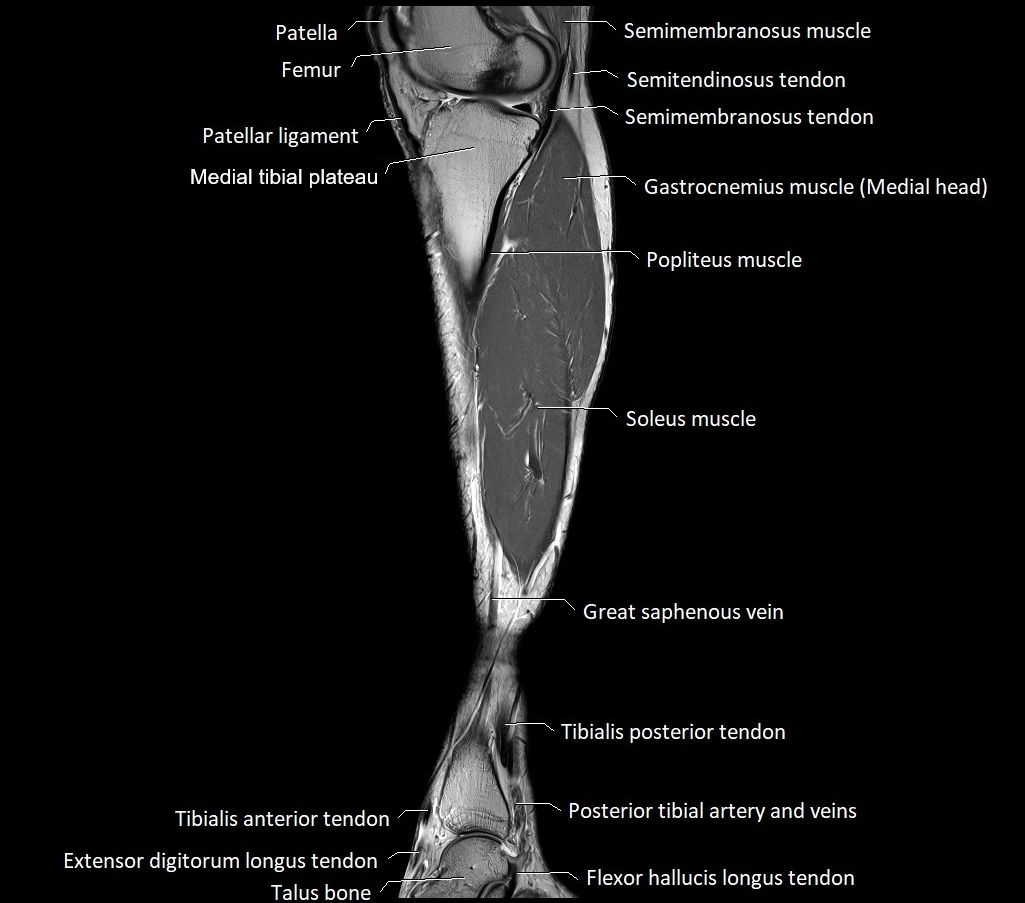

MRI image